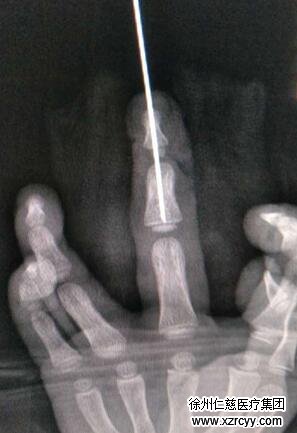

各项术前检查完毕后,晚上6点半左右,鹏鹏被送进了手术室。熊祖国先为鹏鹏的中指进行了清创处理,然后把损伤的血管神经接上。手术是在显微镜下进行的,三岁小孩的中指末节血管直径不到0.2毫米,3个半小时的手术过程中,手术视野的直径也不过5公分,缝合用的线比头发还要细,非常考验医生的细致与耐心。